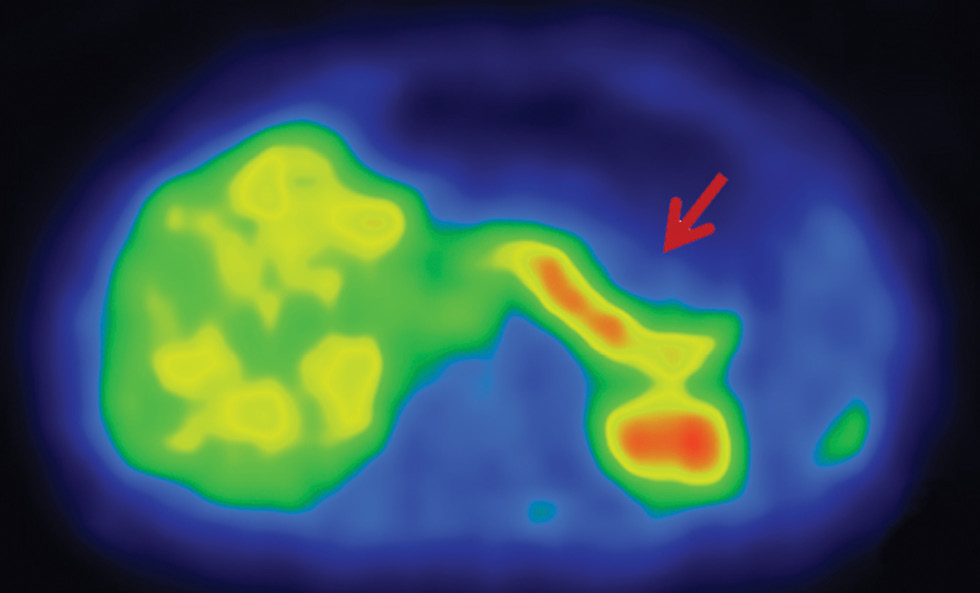

Учитывая принципиальные различия в объеме оперативного вмешательства, пациентам с фармакорезистентным течением ВГИ показано проведение ПЭТ с 18F-ДОФА. Визуализация поджелудочной железы происходит за счет захвата островковыми клетками радиоизотопа [18, 19]. В мировой литературе предлагается применение математического показателя ПИ для оценки результатов ПЭТ. При значении ПИ более 1,5 устанавливается фокальная форма, при значении ПИ менее 1,3 диагностируется диффузная форма ВГИ [20]. Однако на практике существуют определенные затруднения при применении данного параметра для дифференциальной диагностики морфологических форм. В нашем исследовании, несмотря на гистологически подтвержденную фокальную форму, у 1/3 пациентов значение ПИ было менее 1,5. Фокальная форма ВГИ по результатам ПЭТ у данной группы пациентов была предположена исходя из визуальных данных (рис. 3). Значение ПИ было максимальным в промежутках через 20–60 мин после введения радиоизотопа. Таким образом, вызывает сомнения необходимость проведения сканирования через 10 мин после исследования. Затруднения в применении ПИ могут возникнуть за счет физиологического повышенного захвата 18F-ДОФА в области головки поджелудочной железы, при оценке гигантских фокусов или мультифокусов [21, 22].

Рис. 3. Результаты ПЭТ/КТ с 18F-ДОФА у пациентов с различными морфологическими формами ВГИ.

а – диффузная форма ВГИ. Захват 18F-ДОФА равномерен; б – фокальная форма ВГИ. Визуализируется очаг накопления радиофармпрепарата; в – эктопическая локализация фокальной формы ВГИ. Очаг накопления радиоизотопа визуализируется в области двенадцатиперстной кишки.